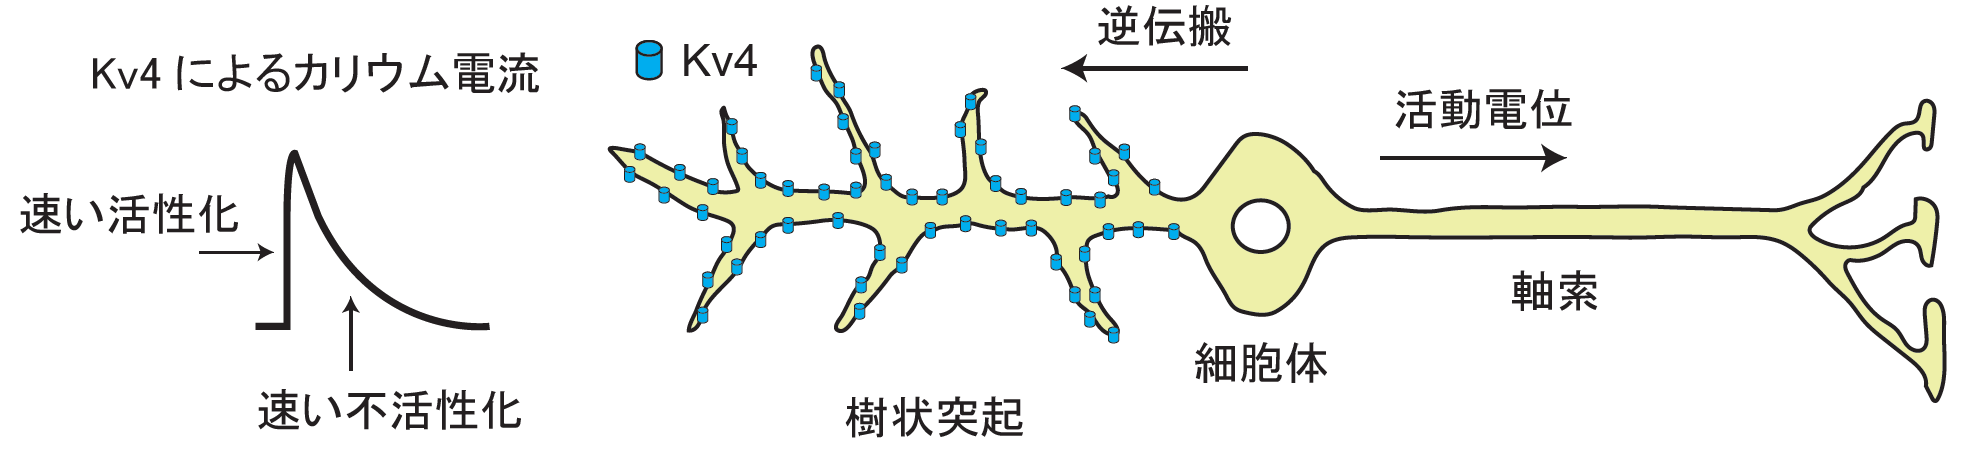

制御サブユニットによるイオンチャネル巨大複合体のモジュレーション機構を解明

神経細胞や心臓の電気活動に必須の役割を果たす電位依存性カリウムチャネル Kv4.2と2種類の制御サブユニット KChIP...